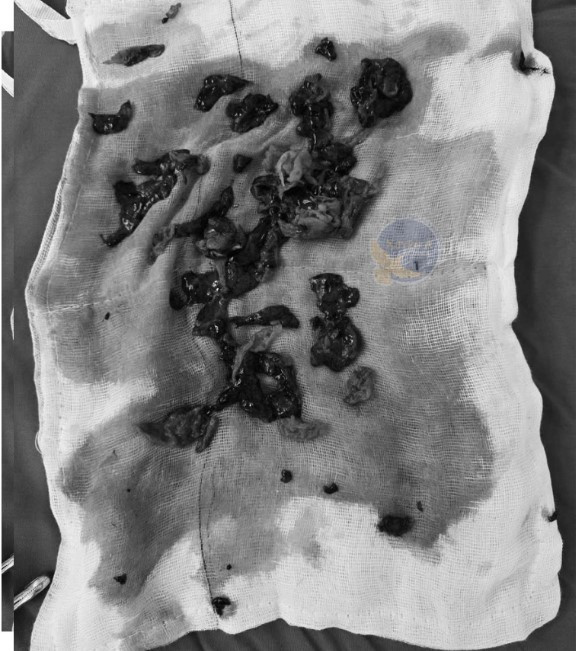

tran-mau-2.jpg

Máu phổi đông đặc được lấy ra - Ảnh BVCC